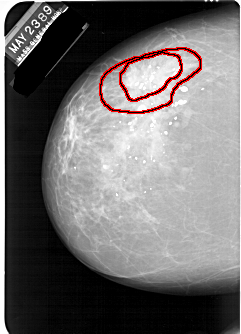

FILE: A_1247_1.LEFT_CC.OVERLAY

TOTAL_ABNORMALITIES 1

ABNORMALITY 1

LESION_TYPE MASS SHAPE IRREGULAR MARGINS SPICULATED

ASSESSMENT 5

SUBTLETY 5

PATHOLOGY MALIGNANT

TOTAL_OUTLINES 2

BOUNDARY

CORE